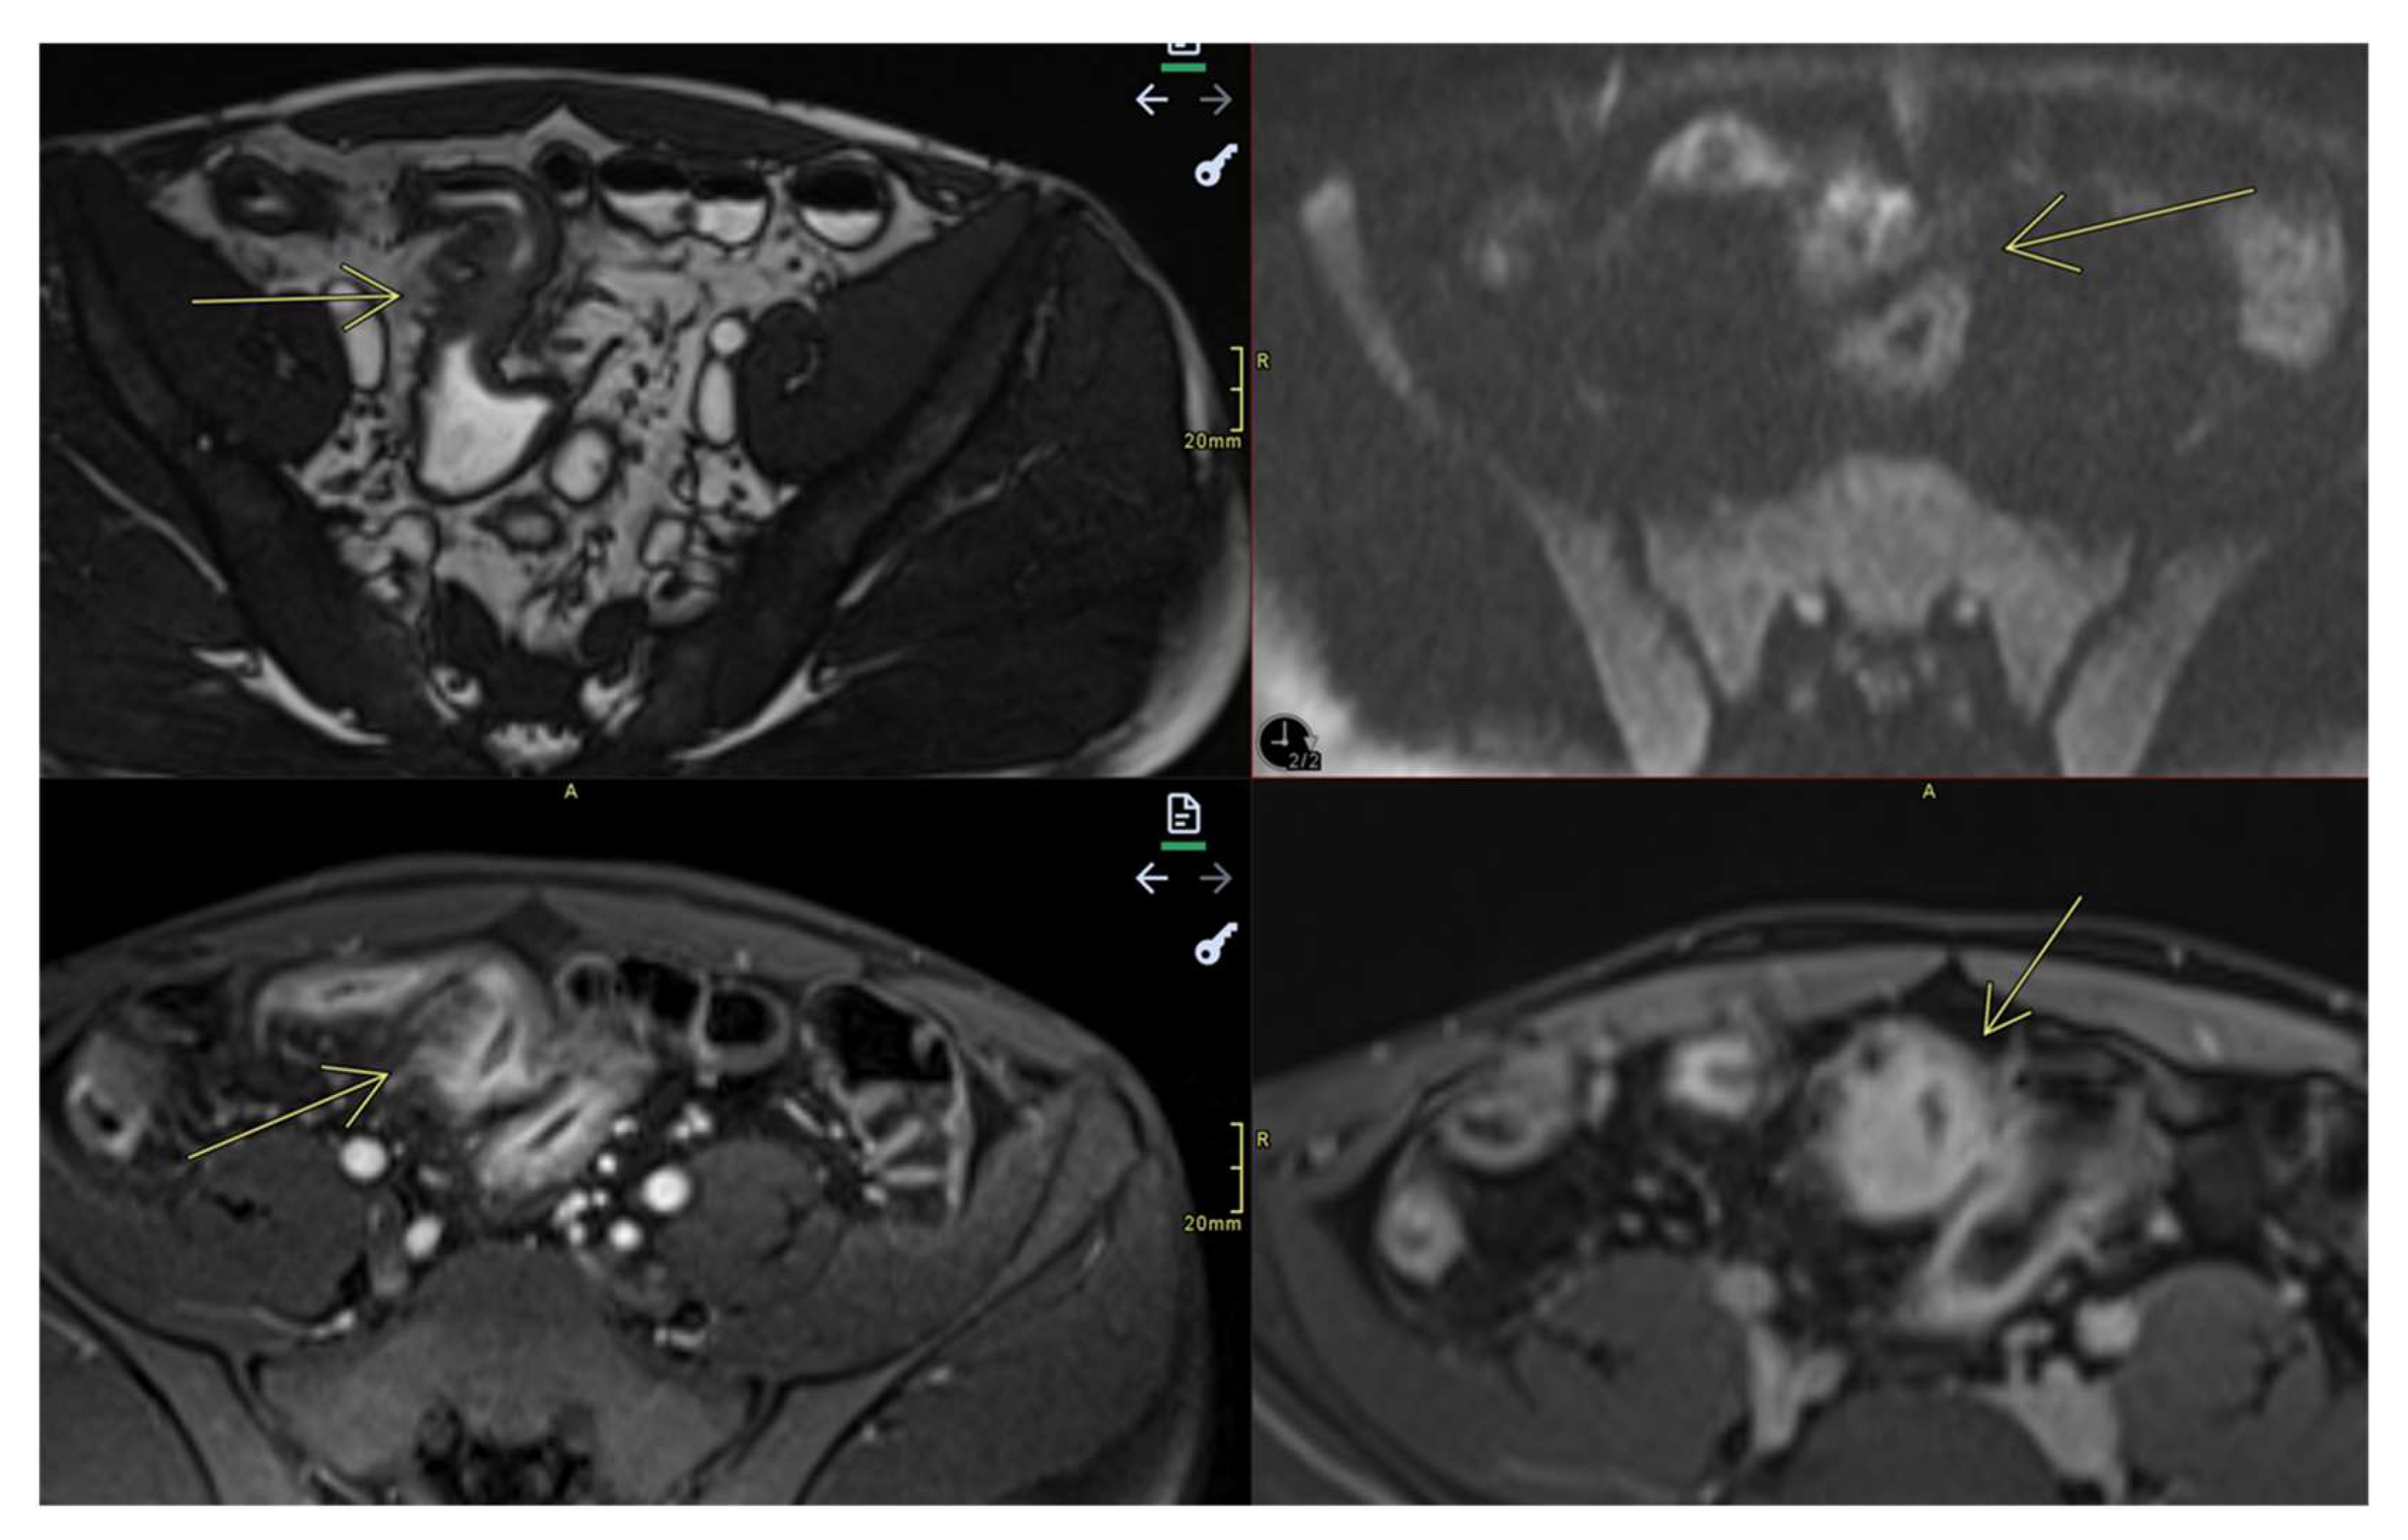

- Fistulas

- They may be enteroenteric, enterocolic, enterovesical, or perianal [8]

- Fistulae occur following advanced penetrating disease [8]